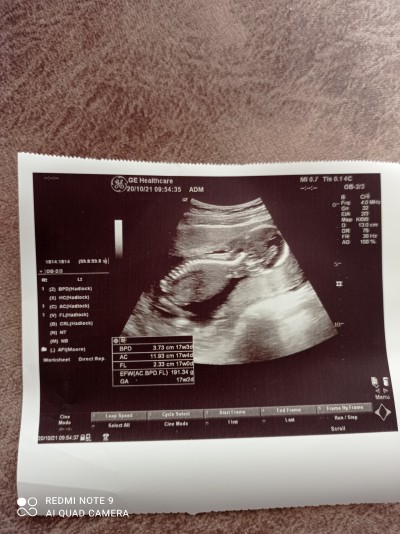

Tahmin alabilir miyim kızlar

Kızlar anlayan tahmin yapabilir mi

Gebelik haftası

16+1 gebelik

erkek bu erkek

Kıza benzettim

Canım bence erkek gibi benim de ultrason resmi şekli aynıydı herkes kız dedi erkek çıktı :)

Erkek gibi cnm

Kız gibi geldi doktor demedi mi canım haftan ileri

Yok pozisyon dan dolayı göremedi canım inşallah 4 gün sonra ögrenicem gösterirse :)

Erkek canım benimkide böyle çok şükür oğlum olacak:)